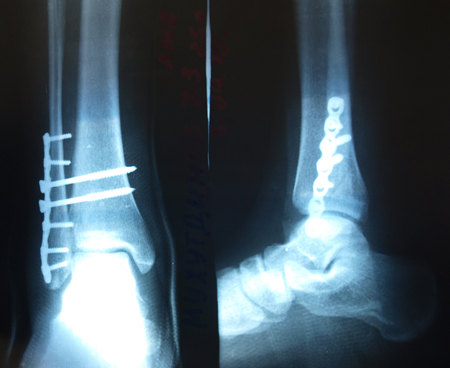

Прямоугольную длинную пластинку поставили на кость, из какой-то дорогущей шведской стали. На семь саморезов. У меня смещения-то не было, лёгкий перелом. Проблема в оторвавшихся связках - их и прикрепили пластинкой. Снимать в октябре-ноябре будут.

Чтобы наглядней было, что было у Тимсона)

Вложения:

000efytp.jpeg

000efytp.jpeg [ 116.72 КБ | Просмотров: 1040 ]